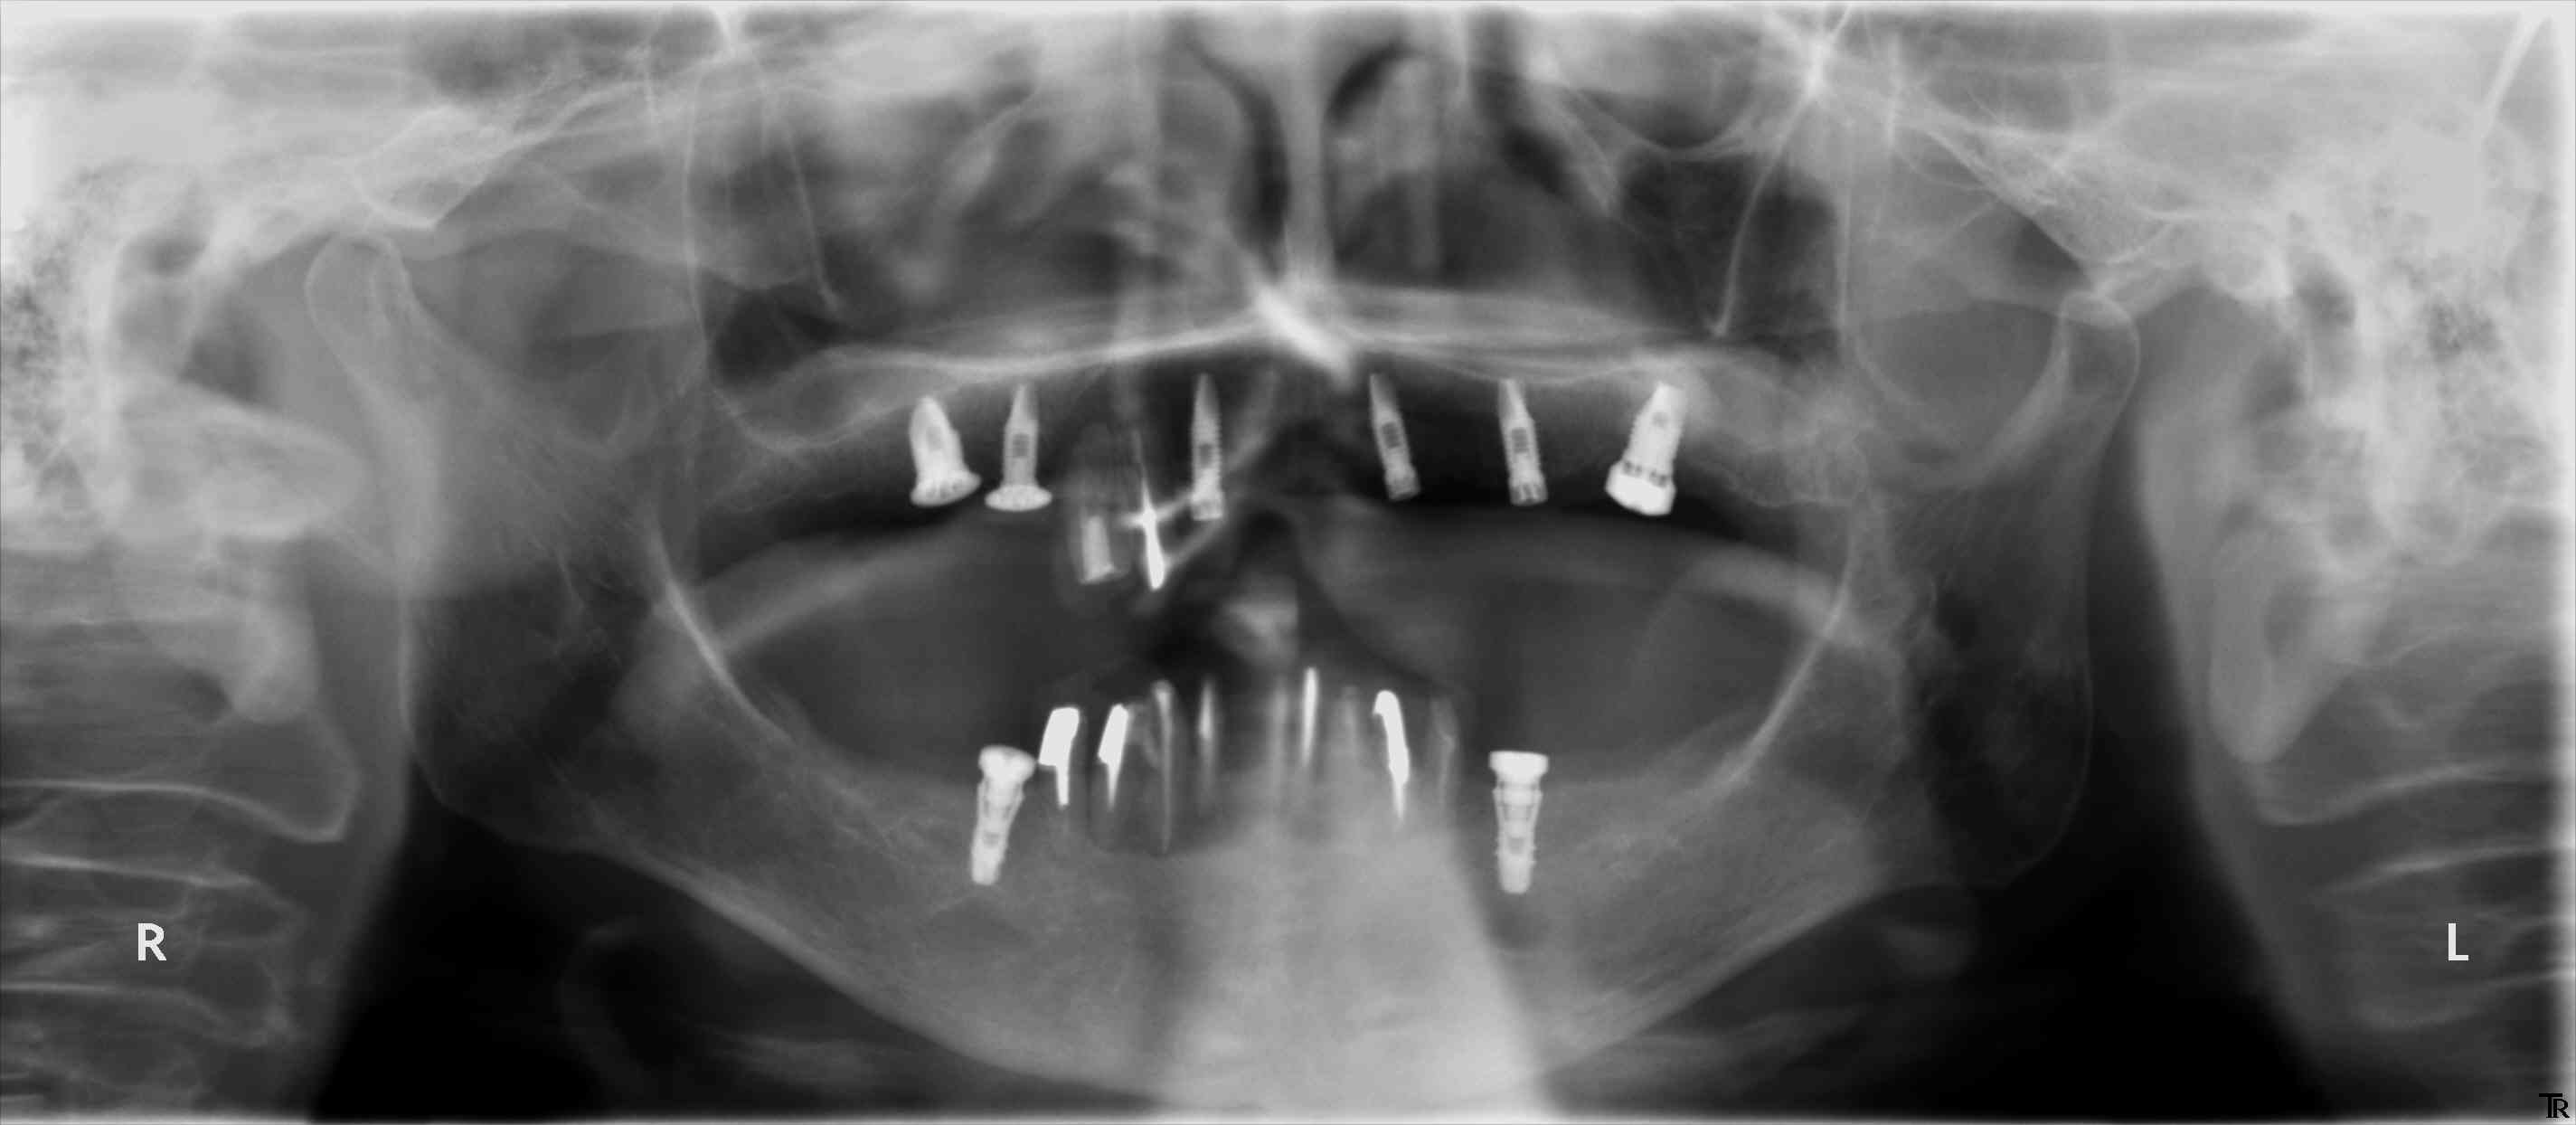

今日の午後は、ストローマンティッシュレベルの埋入でした。

上顎の4番部位の成熟側埋入ですが、欠損部近遠心幅径が7mmとレギュラーネックがぎりぎり使用できる距離です。

審美性を重視される患者さんですので、埋入の3次元的ポジショニングが大切になります。

スタンダードプラスインプラントを使用するため、プロファイルドリルでフレアーを形成します。

最適な埋入深度が得られています。

頬舌側的なポジションもGoodです。